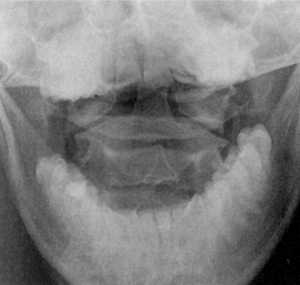

Диагностика. Рентгенография верхнего шейного отдела позвоночника в боковой

проекции выявляет расширение суставной щели Крювелье. В норме расстояние между

задней поверхностью передней дуги атланта и передней поверхностью зубовидного

отростка аксиса равняется: в положении сгибания -1,8 мм, разгибания - 2,2 мм,

в нейтральном положении - не более 2 мм (Hinck, Hopkins, 1960).

КТ и цифровая спондилография - важные методы диагностики вывихов атланта (рис.

1.7 и 1.8). МРТ позволяет определить не только дислокацию атланта, но и степень

компрессии спинного мозга (рис. 1.9).

Рис 1.7. Ротационный вывих атланта по

данным цифровой спондилографии |

Рис. 1.8. Вывих в атланто-аксиальном сочленении по данным

цифровой спондилографии |